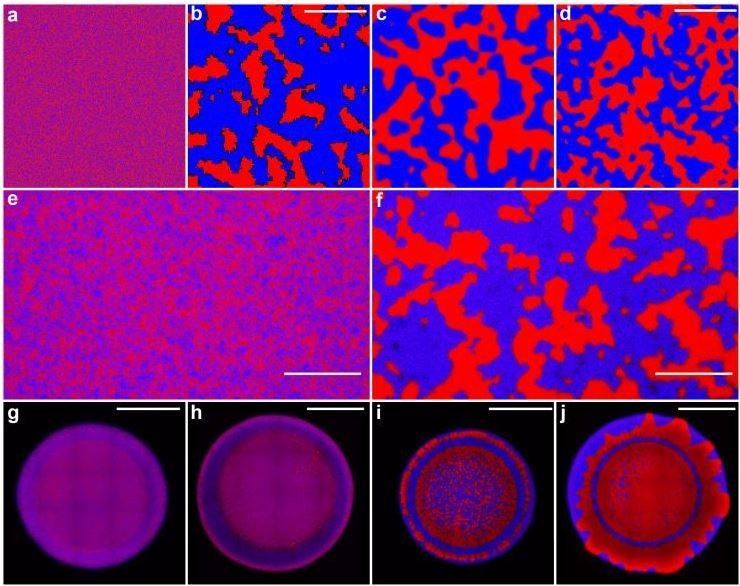

How armies of stabbing bacteria could transform healthcare http://wef.ch/2l3iY9j pic.twitter.com/MBaZ0nRLkh